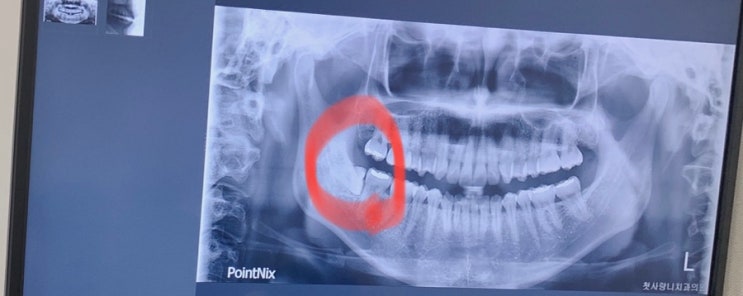

[사랑니 발치] 첫사랑니 치과 매복사랑니 발치 내돈내산 추천 후기

#매복사랑니#사랑니발치#부산치과 집 근처에서 치과에서 추천받은 '첫사랑니치과' 예약 후 2주를...